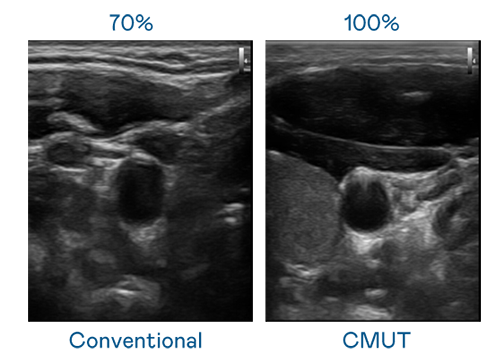

CMUT 技術是一種用電容式微機電元件來產生超音波訊號的技術。與傳統 PZT 壓電式技術相比,CMUT 頻寬增加 30%,更寬頻的超音波訊號讓影像解析度大幅提升,是實現高影像品質醫療超音波掃描、促進精準醫療發展的關鍵技術。

大頻寬帶來超清晰影像

超音波影像的解析度高低,首先取決於探頭能發出的訊號頻寬。rb88随行版 CMUT 可提供高清晰的超音波訊號,提供高頻寬、高靈敏度、影像紋理細節更高的超音波影像,協助醫護人員縮短影像判讀時間及利用精準的醫療影像進行診斷。